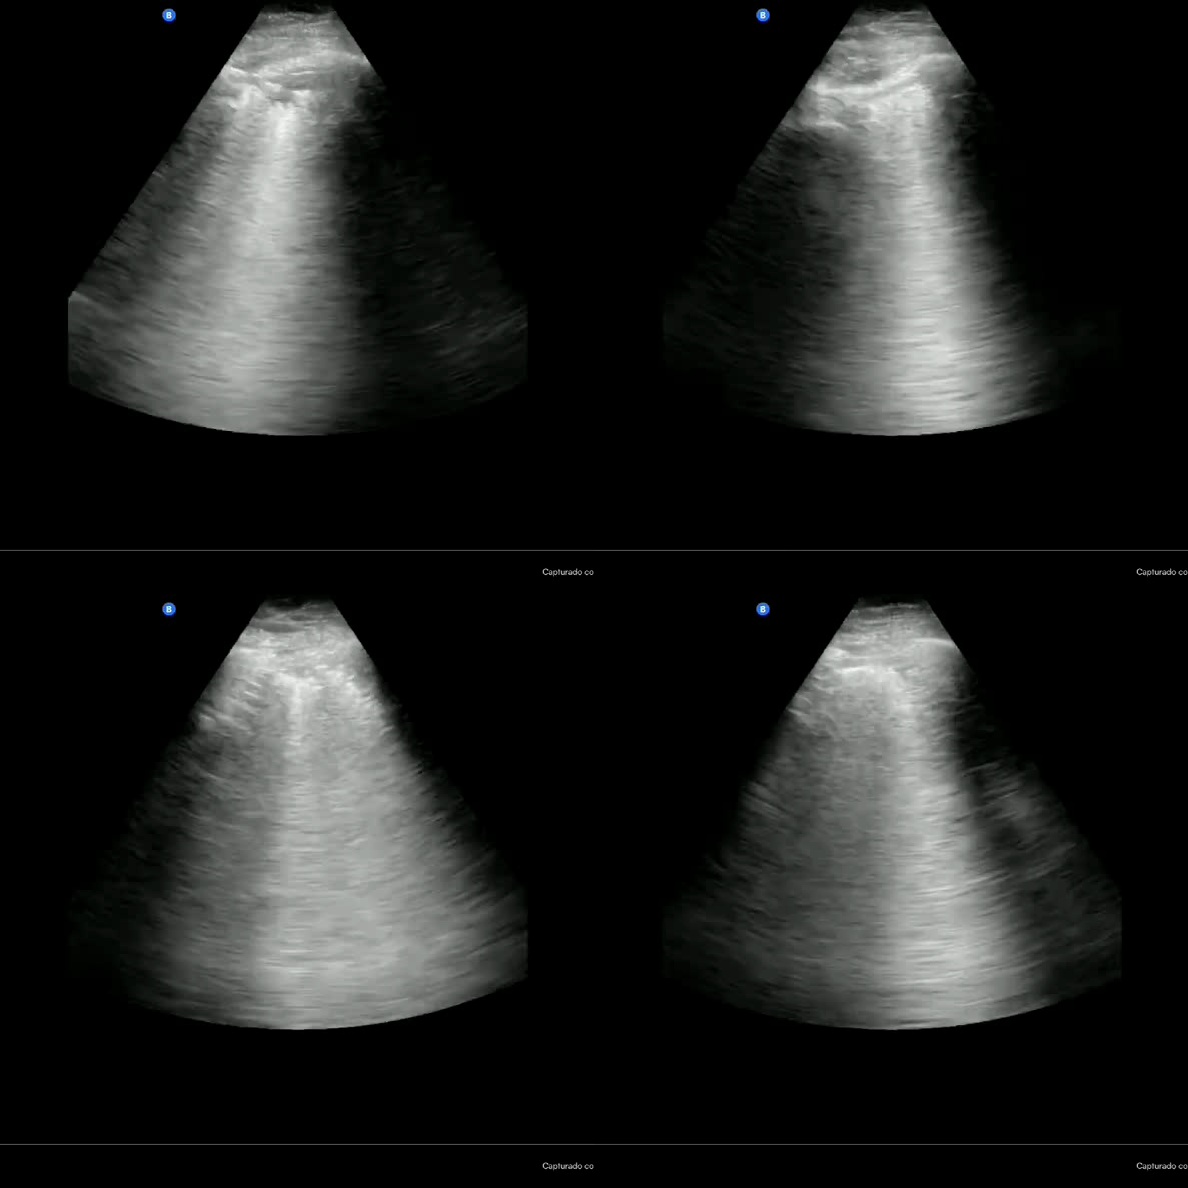

Refer to caption

Figure 4: Model outputs annotated by clinical experts. QoQ-Med correctly reasons from modality-specific clinical knowledge, generates bounding boxes, and outputs the correct predictions in most instances except (c). (e) demonstrates the model’s ability to synthesize multimodal inputs with reasoning. The bounding boxes correctly highlight the salient regions related to the reasoning steps when one is present.

Clinician relevance annotations. App. D.4.2 provides a breakdown of clinician-annotated reasoning traces, revealing that the model mostly generates contents highly relevant to the diagnosis, with minimal output judged as irrelevant. We observe that the model often correctly recalls relevant clinical knowledge, which help guide the model by providing associative context. For example, in Fig  4(a), the model correctly recalls different signs of hemorrhage on CT, such as darker or whiter tissues, and relates this context to specific parts of the image to make a correct prediction. In Fig. 4(c), the model correctly identifies the presence of a pacemaker, indicating a support device, but subsequently concludes that there are no additional abnormalities, ultimately leading it to predict “No finding”. This suggests that while the model’s final predictions may be incorrect, its intermediate reasoning often reflects clinically relevant patterns.

Bounding box quality. Fig. 3(b) demonstrates that the model identifies bounding boxes correlated with the ground truth annotations, with the IoU exceeding the best open source models while reaching a similar performance as the closed-source reasoning model o4-mini. From Fig. 4, we also see that the outputs by the model are sufficiently aligned with the reasoning process, allowing the clinicians to confirm the model’s predictions while cross-referencing the source image.